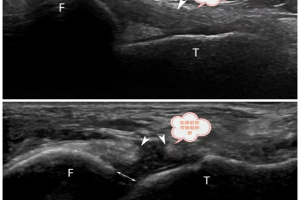

在日常生活中,肌肉拉伤、关节疼痛常常影响着我们的生活质量,而准确诊断出病因是有效治疗的关键一步。今天,就来给大家介绍一项神奇的检查技术——肌骨超声。 什么是肌骨超声? 肌骨超声是一种新型、无创且便捷的超声检查技术,它就像医生的“透视眼”,能够清晰地看到肌肉、骨骼、肌腱、韧带、关节等结构及其周围组织的细微变化。